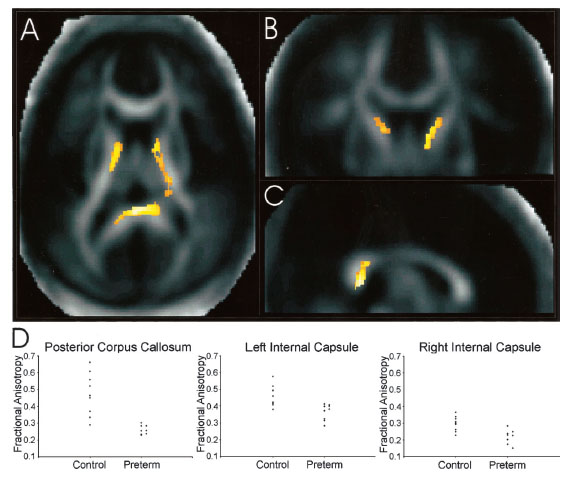

En otro estudio del proyecto Neonatal de Estocolmo, utilizando imágenes de tensión de difusión, se encontrarón alteraciones en la sustancia blanca durante la adolescencia, en particular en el cuerpo callosal y la capsula interna, Nagy et al. 2003 (12). Estas alteraciones fueron asociadas con problemas de inatención.